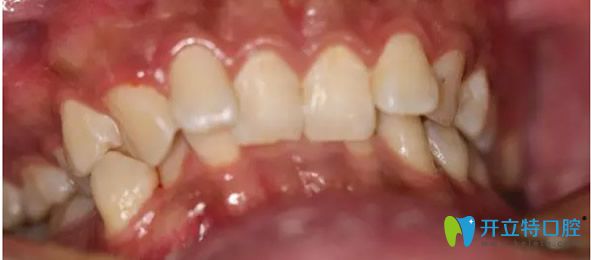

先看看我在武漢愛齒爾口腔矯正牙齒前的照片:

武漢愛齒爾口腔矯正牙齒前

到后,龐勇主任幫我做了牙齒CT,發(fā)現(xiàn)我牙齒不齊且伴有深覆合現(xiàn)象,很影響美觀。但我又不愿意拔牙矯正。醫(yī)生就為我制定了3M自鎖托槽矯正牙齒的方案。于是我的正畸之路就開始了。